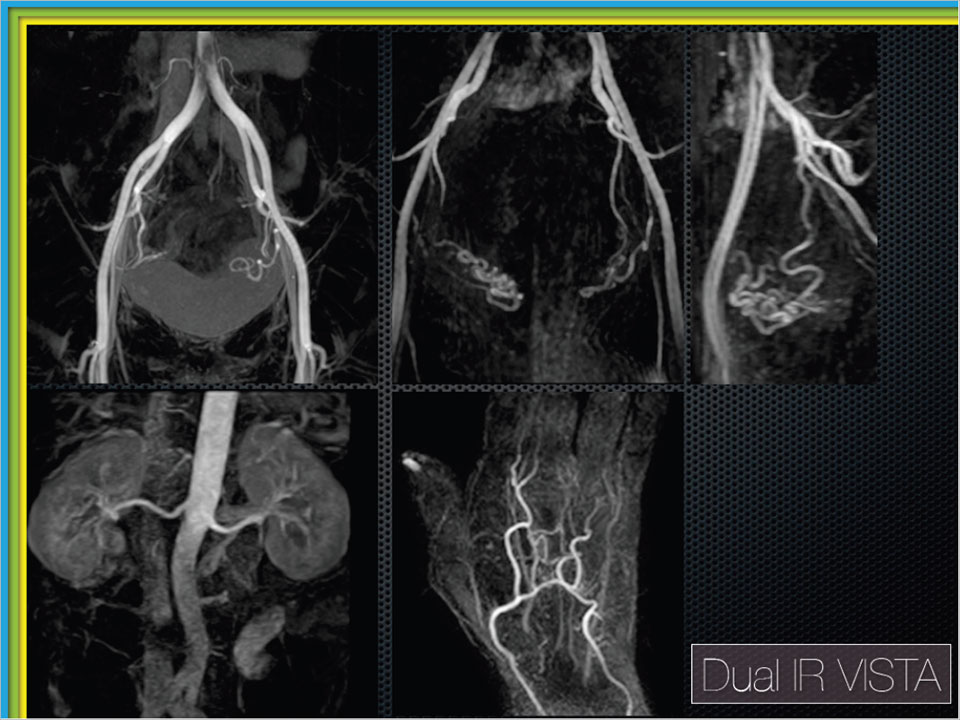

従来の非造影 MRA には、TOF 法や PC 法を用いた MRA や、TSE シーケンスを用いた TRANCE 法、balanced シーケンスを使用した MRA などがありました。今回、中村先生は全く新しい非造影の MRA を考案されました。 その方法とは、頭部領域にて白質画像(WM only)や灰白質画像(GM only)を選択的に描出する際に用いる Dual IR シーケンスを VISTA に併用した MRA です。MRA においては動脈以外の背景信号を抑制することは重要です。そこで、Dual IR シーケンスを使用することで、実質組織と水信号の Null point が合致するタイミングを模索し、見事抑制することに成功しました。 動脈血に関しては、常に新しい血液が流入してきますので、高い信号を保持することができますが、静脈血に関しては血流が遅いことから実質組織のように停滞していますので、低信号となります。これにより動脈と静脈を選択的に描出することが可能となります。また、VISTA を使用していることから、磁化率や乱流の影響にも強いということで、頸部などにも有用です。 撮像条件は、1.5T にて TR = 3000ms で、頭頸部領域においては 1st TI = 1800ms、2nd TI = 400ms となります。上腹部・骨盤部領域では抑制する組織も頭頸部領域とは変わってくるため、1st TI = 1980ms、2nd TI = 180ms となります。この条件を用いることで、今までにない新しい非造影MRAを撮像することが可能となります。